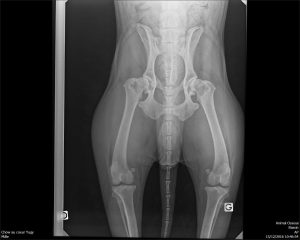

Jeudi 15 décembre: C’est le jour de la castration pour Yugi. Comme à chaque fois que quelque chose nous semble poser problème, nous profitons de l’anesthésie pour faire examiner le chien sous toutes les coutures; concernant Yugi nous avons constaté un œil qui pleure beaucoup et une forte sensibilité de l’arrière-train, tant lorsqu’il s’assied que lorsqu’on tente de le brosser. Bingo!

- Entropion de l’oeil droit avec ulcération de la cornée, Yugi a perdu environ 60% de son champs de vision. L’autre œil va bien.

- Dysplasie bilatérale des hanches; la vétérinaire ne conseille pas d’opérer mais d’aider Yugi à maintenir ce qu’il reste de son capital osseux avec des chondro-protecteurs et d’atténuer ses douleurs avec ponctuellement des anti-inflammatoires.